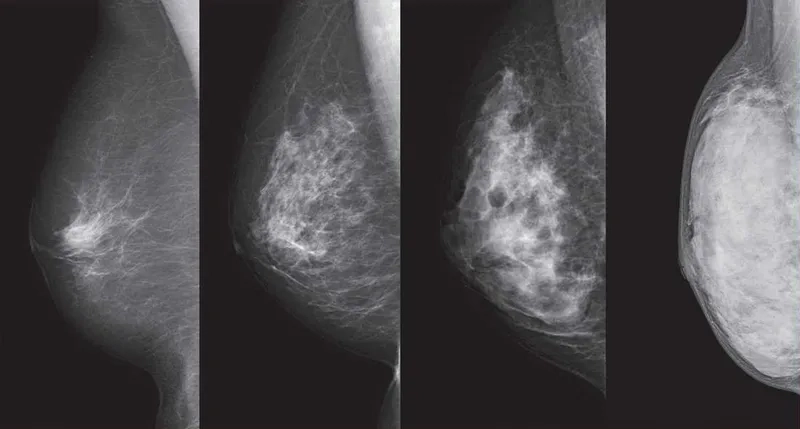

• Regular screening with mammograms is crucial for early detection, as they can identify cancer before symptoms appear, improving the breast cancer survival rate.

An illustration of the different breast cancer stages